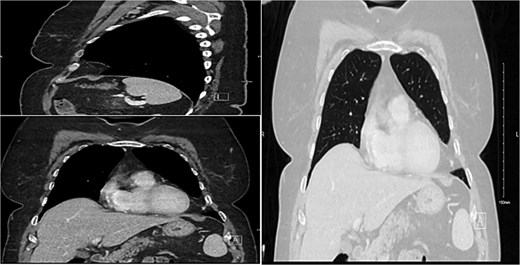

This is a 56-year-old female referred to our clinic with on-and-off left pleuritic chest pain since 3 months. Her past medical history was significant for hypothyroidism and dyslipidaemia. Upon presentation, she was conscious, alert, oriented, with normal vital signs, not in respiratory distress. Her laboratory workup unremarkable, chest X-ray was unremarkable for any abnormality, and computed tomography scan of the chest with IV contrast (Fig. 1) showed features suggestive of benign left pleural lipoma with no effusion or pleural thickening. Preoperative tests were done, the patient underwent surgical resection via VATS by a 10-year expert consultant. The operation was done uneventfully and specimen was sent to laboratory that revealed the diagnosis of pleural lipoma (Fig. 2). Patient postoperative period was uneventful, discharged after surgery and followed up in clinic for 1 month with resolving of her symptoms completely and return to her normal life activities safely.

Demonstration of a pleural-based soft tissue mass consistent with lipoma.